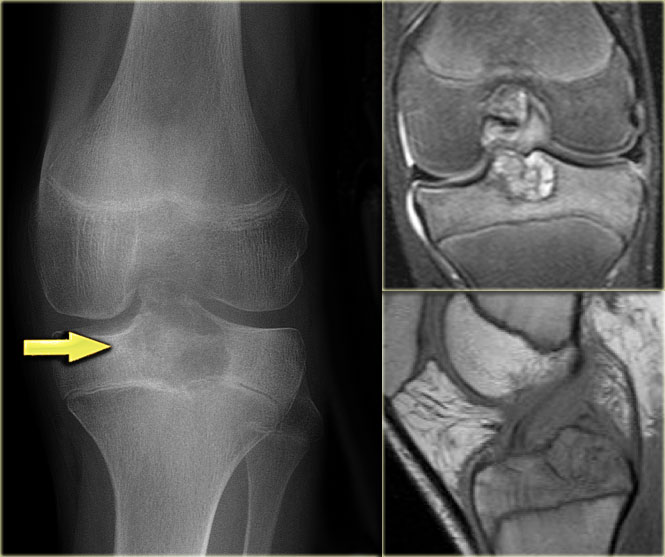

On the left more examples of GCT around the knee.

Notice that most of these lesions are well-defined and located in the epiphysis and extend into the metaphysis.

Some extend onto the articular surface (yellow arrow and small red arrows).

The lesion on the upper right has an ill-defined border with a broad zone of transition (blue arrow).